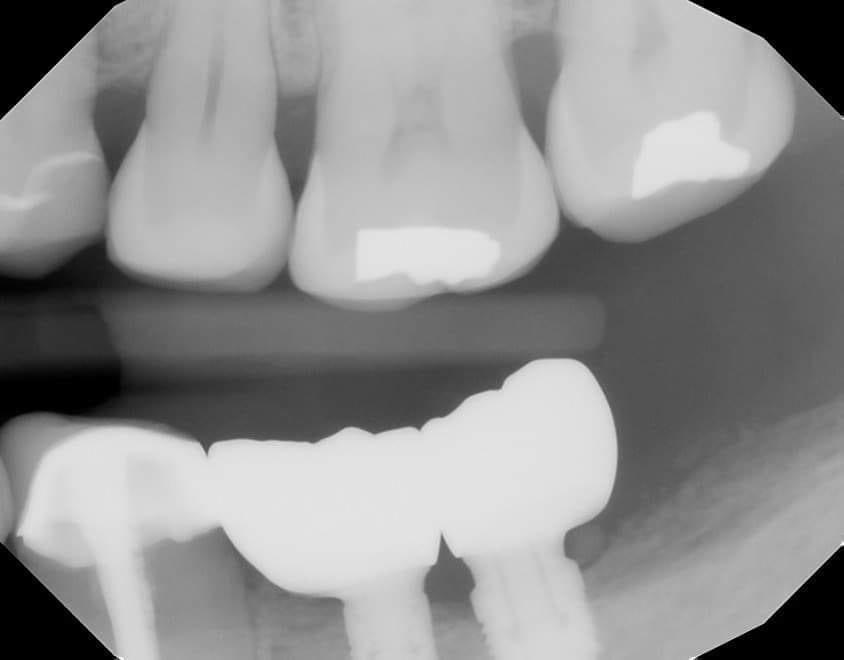

You would have struggle with analog impressions

This is THE indication for digital dentistry over analog impressions!